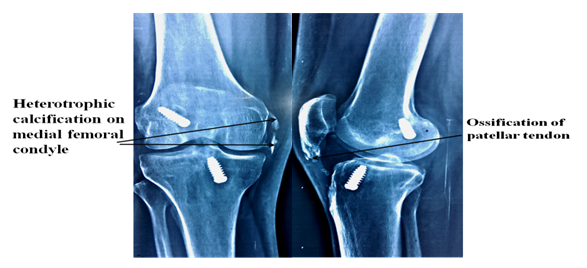

BPTB graft is considered as a gold standard graft for ACLR because of better knee stabilty1,2 and higher return to sports after ACL reconstruction with BPTB graft.1,3,4 However, BPTB graft is criticized for donor site morbidity like anterior knee pain, patellar fracture, quadriceps tendon rupture etc.5−7 Among the variously described complication of BPTB graft, patellar tendon ossification is one such rare complication. Patellar tendon ossification has been reported mainly in patients with knee injury,8 total knee replacement,9 partial patellectomy,10,11 intramedullary nail12 and after spinal cord injury.13  Patellar tendon ossification after ACLR is extremely rare. This complication has been reported by only few studies in literature14−18 (Table 1). The cause of patellar tendon ossification is not cleared. Gianluca Camillieri et al.16 gave hypothesis that persistence of bone debris inside the patellar tendon may trigger calcification. However, they did not have an immediate postoperative x-ray to prove their hypothesis. In the present case report, we had postoperative CT scan (5th day) which showed the loose bone fragments in the joint (Figure 2) which support the hypothesis given by Gianluca Camillieri et al.16 & Erdogan et al.19 gave another hypothesis he believed aggressive rehabilitation causes microtrauma within patellar tendon.19 However same rehabilitation protocol was followed by others patients and none of them showed patellar tendon ossification. Another possible pathogenesis given by Bonamo et al.20 he stated that devascularization of the graft during harvested results in avascular necrosis. Heterotrophic ossification is commonly encountered problem in orthopaedics. The incidence of heterotrophic ossification after ACL reconstruction with BPTB graft vary from 1.54%-2.58%.21 Mohamed A et al.22 observed that incidence of bone debris after ACL reconstruction surgery was 15% if thorough debridement was done and 65% if no specific debridement protocol was followed.22 Treatment of patellar tendon ossification is still not well established. However, some authors showed good results with surgical resection of ossification.14 We managed our patient non-operatively as he did not have any limitation of daily activity. In the present case report, we observed that patient had both patellar tendon ossification and heterotrophic ossification. There was no case reported in the literature which showed both patellar tendon ossification and heterotrophic calcification in the same patient after ACL reconstruction with BPTB graft.

Figure 2 Post-operative (5th day) CT scan showing loose bone debris in the joint.